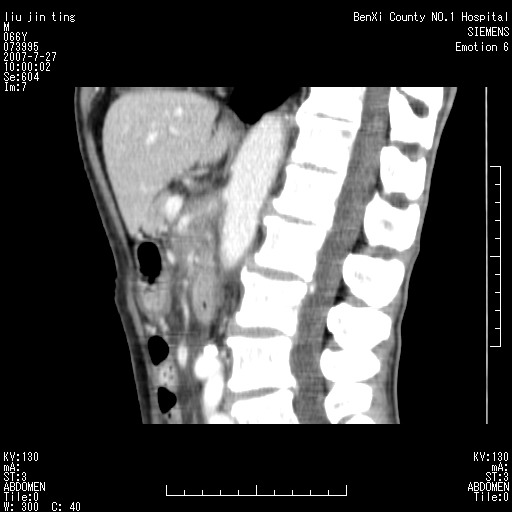

腹痛,背痛,无恶心呕吐,不黄,彩超示胰腺钩癌,ct扫描病灶平扫30-40hu,增强后动脉期40--60hu,静脉期50-68hu,真的是钩突上的么?您要试一试么?

沿着肠系膜上动脉呈匍匐性生长的软组织肿块,形态不规则,包绕肠系膜上动脉,呈明显强化,考虑来源于肠系膜的恶性肿瘤

沿着肠系膜上动脉呈匍匐性生长的软组织肿块,形态不规则,包绕肠系膜上动脉,呈轻-中度强化,考虑来源于肠系膜的恶性肿瘤。

支持!恶性纤维组织细胞瘤可能,与淋巴瘤及淋巴结转移鉴别(腹主动脉周围清晰,其他部位亦未见明显肿大淋巴结)。

考虑为腹膜后恶性纤维组织细胞瘤。

后腹膜肿块,包围血管,考虑淋巴恶性病变,淋巴瘤或转移。